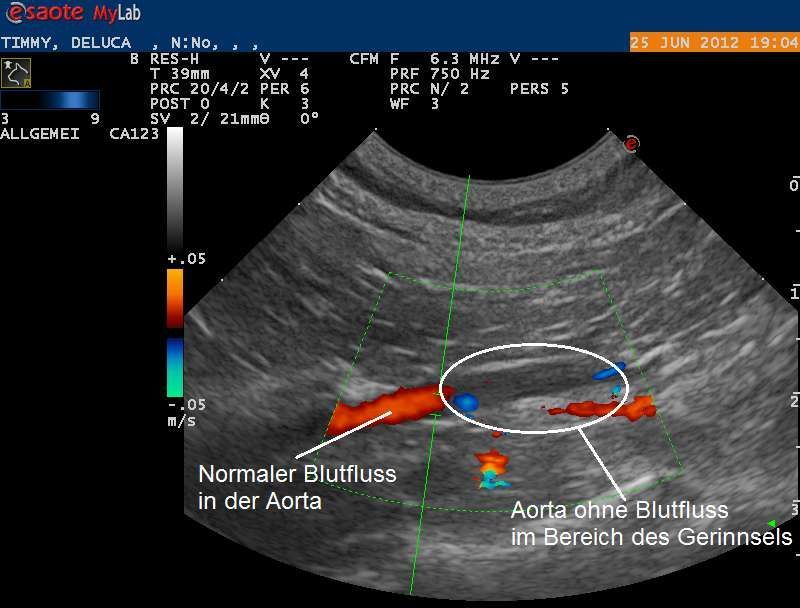

Nun wird die Körperschlagader mittels Ultraschall genauer untersucht. Diese zweigt sich vor dem Beckeneingang unter anderem in die beiden Schenkelarterien auf und versorgt so die Gewebe der Hinterbeine mit Sauerstoff. Eine Doppler-Ultraschalluntersuchung zeigt, dass die Körperschlagader nicht mehr komplett durchgängig ist und nur noch sehr wenig Blut die Beinarterien erreicht. Beim Doppler-Ultraschall kann fliessendes Blut farbcodiert dargestellt werden und so Hindernisse in einem Gefäss dokumentiert werden.

Die beiden Schenkelarterien werden mittels Ultraschall ebenfalls lokalisiert - sie zeigen aber aufgrund der Blockade in der Körperschlagader wie befürchtet nur einen sehr geringen Blutfluss.